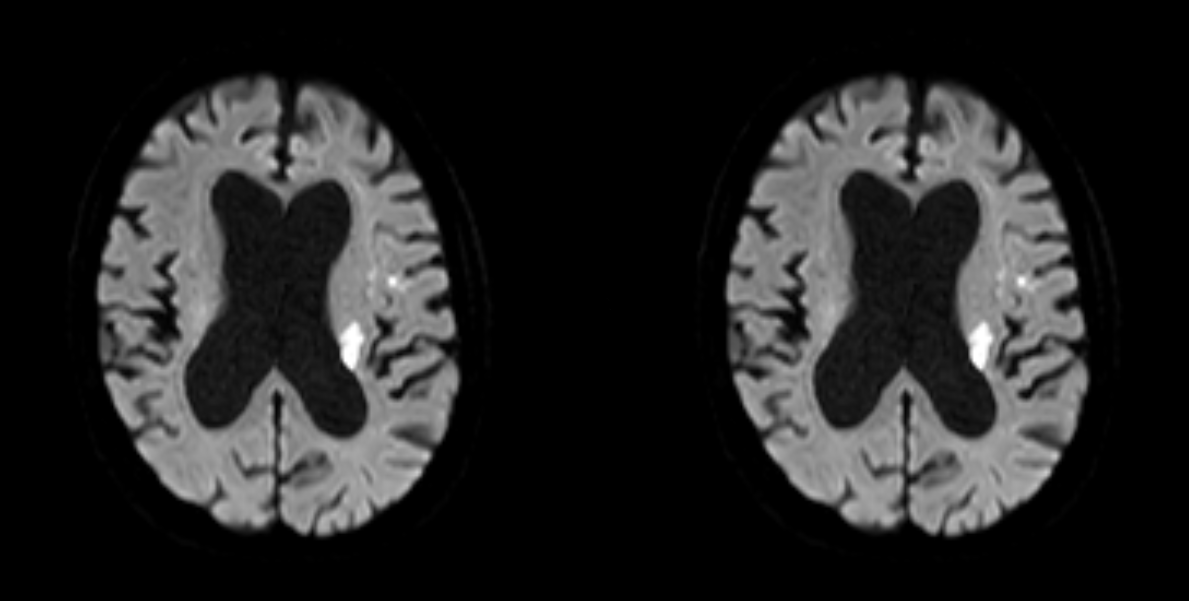

ABSTRACT is a pioneering research study which aims to use the power of Artificial Intelligence to make better predictions about who will develop a stroke in the future. By analysing information held in healthcare records and medical tests, we aim to produce personalised assessments of the risk of future stroke, enabling healthcare professionals to offer treatment to reduce this risk. To find out more click here.